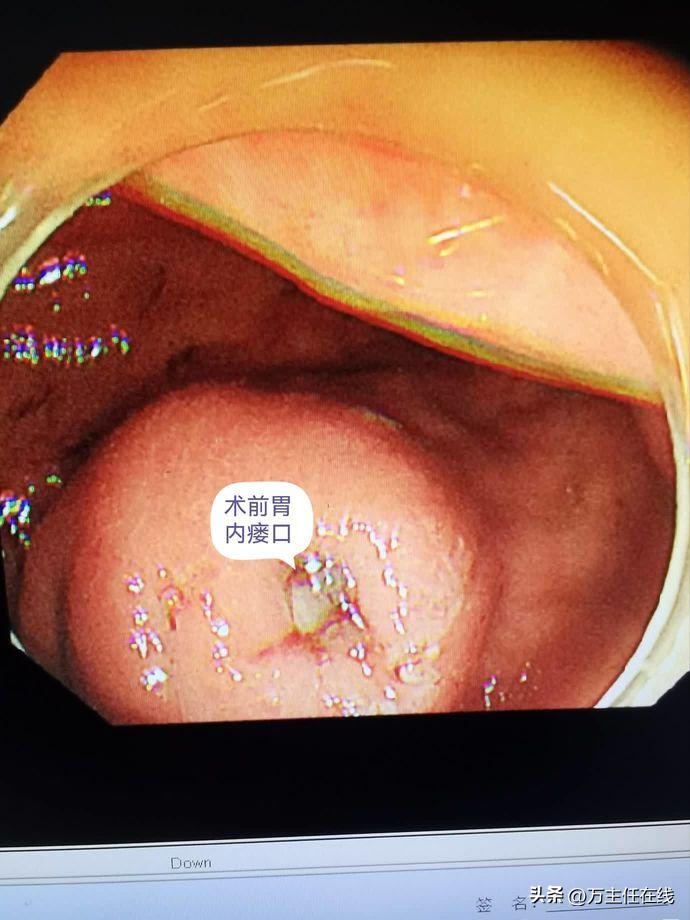

术前内镜探查见胃腔内多发瘘口形成并有少量粘液自腹腔瘘入

胃窦后壁受压,胃腔梗阻;超声内镜引导下胃窦后壁穿刺避开肠管及重要血管留置导丝于腹腔